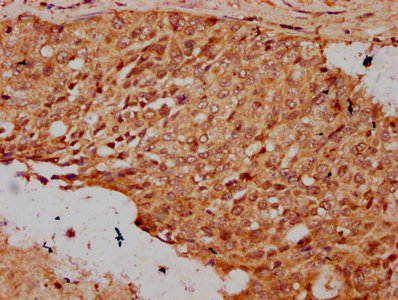

IHC (Immunohistochemistry)

(IHC image of AAA235097 diluted at 1:20 and staining in paraffin-embedded human cervical cancer performed on a Leica BondTM system. After dewaxing and hydration, antigen retrieval was mediated by high pressure in a citrate buffer (pH 6.0). Section was blocked with 10% normal goat serum 30min at RT. Then primary antibody (1% BSA) was incubated at 4 degree C overnight. The primary is detected by a biotinylated secondary antibody and visualized using an HRP conjugated SP system.)